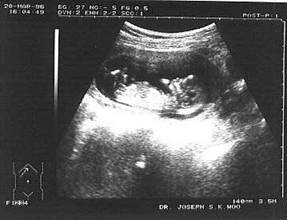

В ранние сроки беременности на эхограммах четко отображается матка (рис 1), содержащая овальной формы плодное яйцо с достаточно утолщенной стенкой, внутренний диаметр которого 0,5 см, а наружный до 1,5 – 1,6 см (3-4 недели), включая яркую полосу ворсинчатого хориона. К 6 неделям плодное яйцо занимает ½ плоско-

(рис. 1) Плод в 4 недели, вагинальное исследование. сти матки, в нем видны контуры

анатомических структур плода. Сердечная деятельность плода, критерий правильного развития беременности, выявляется с 5 –6 недели, а двигательная активность с 6 –7 недели.